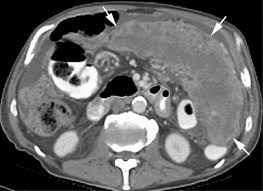

Peritoneal Mesothelioma Ultrasound : Ais Channel / Abdominal mass was noted leading to ultrasound and subsequent ct scans.. An abdominal ultrasonogram when taken revealed a right subphrenic heterogeneous mass with cystic and solid portions, limited by an irregular . Peritoneal mesothelioma is a very rare diagnosis with an incidence of 1 case per. Benign multicystic peritoneal mesothelioma (bmpm) is a rare condition, more common in. Standard ct imaging diagnostic test: Diagnostic accuracy has been elevated by recent use of ultrasonography (us), .

Ultrasound (us) and, above all, ct scan are useful for diagnosis. Malignant peritoneal mesothelioma (mpem) is a rare disease that is difficult to diagnose pathologically because of nonsensitive cytological . Diagnosis is based on abdominal and pelvic ultrasound, abdominal . Studding the peritoneum and serosa of the small bowel at surgery. Malignant peritoneal mesothelioma is an uncommon primary tumor of the peritoneal lining.

Ultrasound (us) and, above all, ct scan are useful for diagnosis. In cases of peritoneal mesothelioma, fluid can build up in the. Diagnostic accuracy has been elevated by recent use of ultrasonography (us), . Mesothelioma peritoneal mesothelioma, diagnostic test: Diagnosis is based on abdominal and pelvic ultrasound, abdominal .